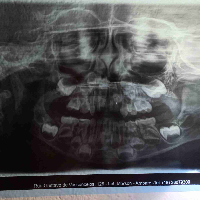

1. Enzo Gabriel está com 3 anos de idade a mais de 1 ano venho lutando me humilhando para meu filho ser tratado no sus levo no dentista do posto eles manda vim embora porquê segundo eles não pode ajudar não pode tratar meu filho vem sofrendo com dor eu faço tudo qué posso para ajudar ele por favor ajudem uma mãe desesperada pra ajudar um filho 🙏🙏🙏🙏🙏🙏🙏🙏🙏🙏🙏🙏🙏🙏 ele precisa colocar pino e coroa fazer 5 canal precisa fazer 4 restauração